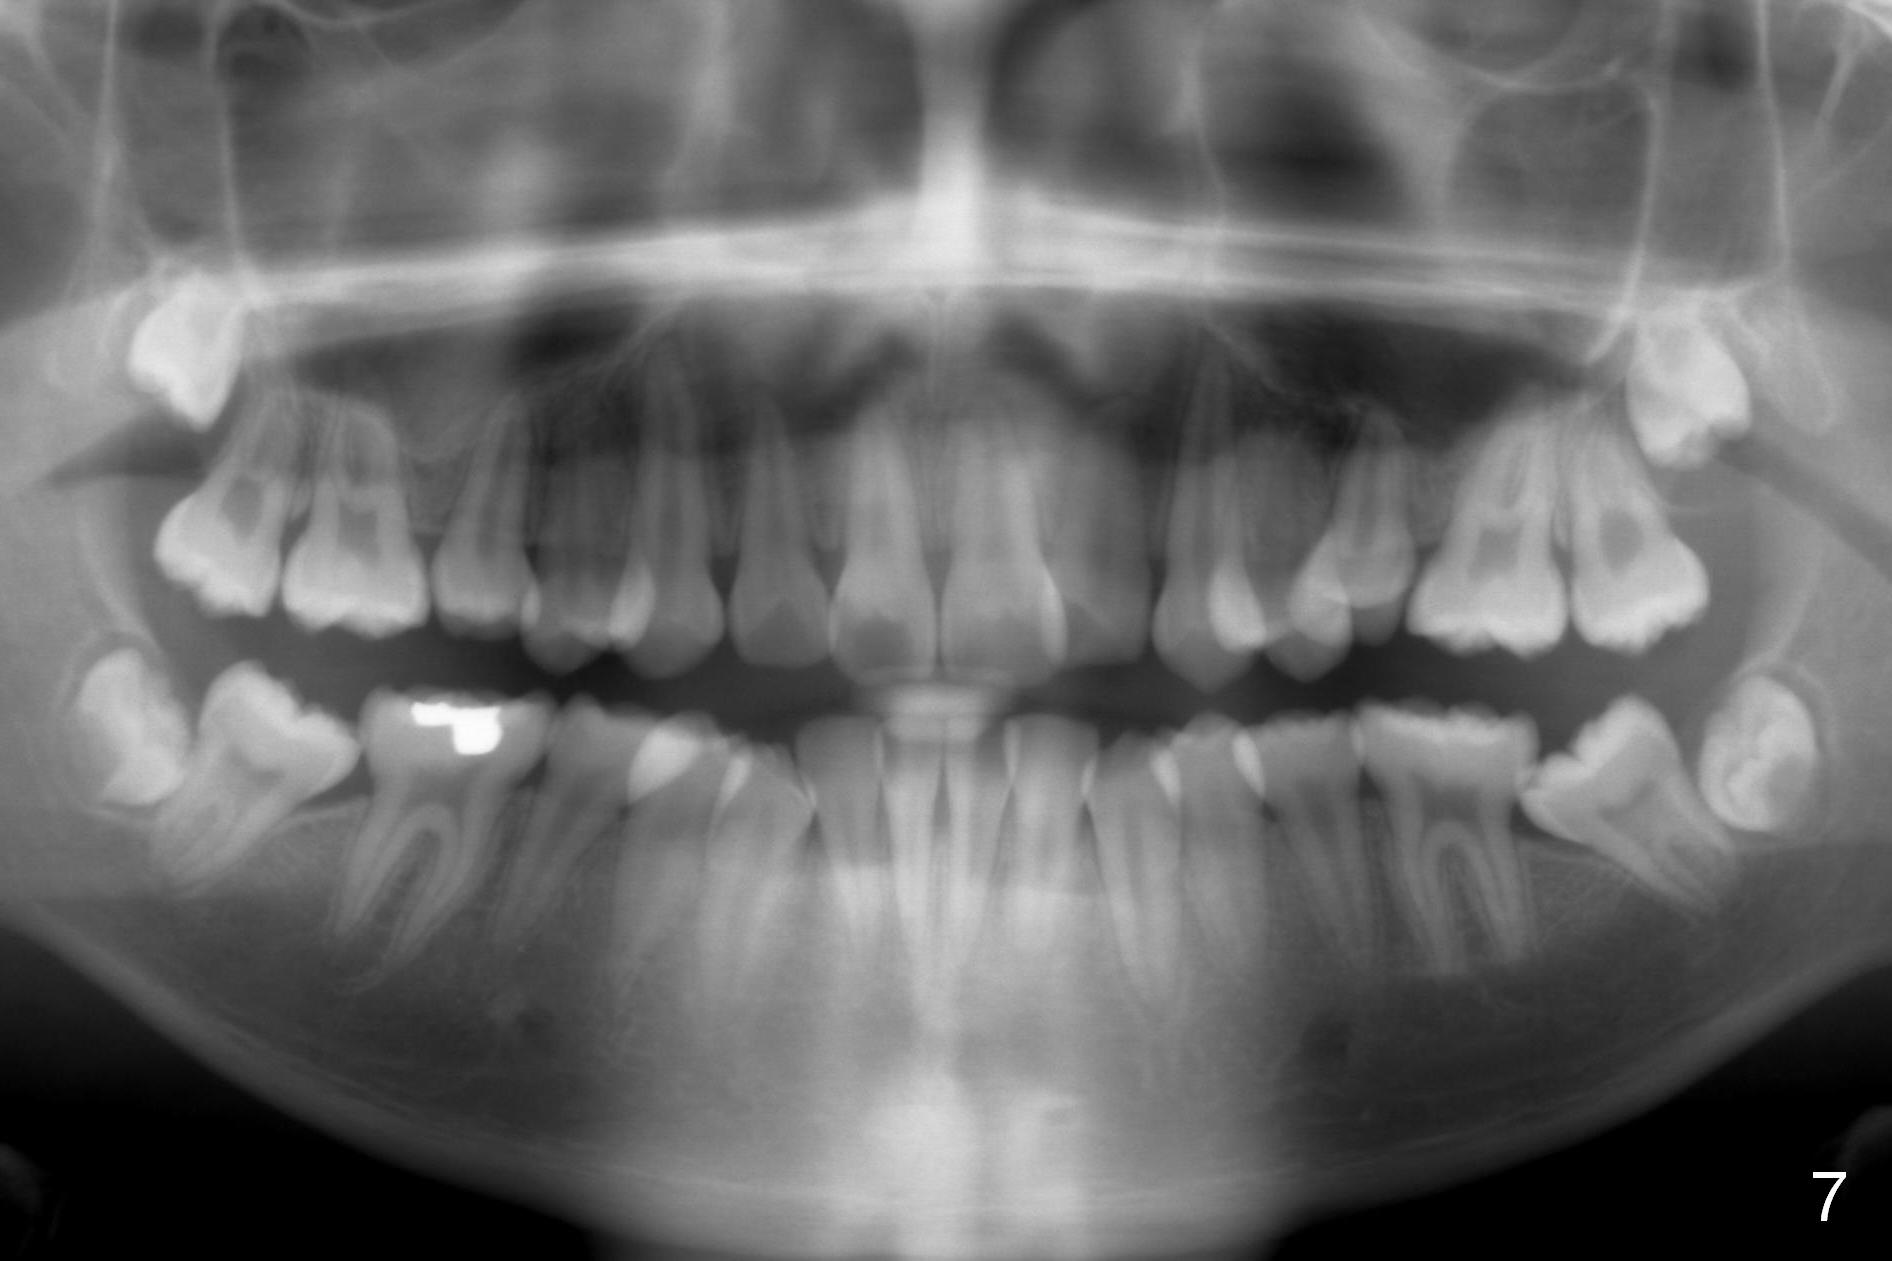

How to Take Before and After Photos for Orthodontics

First of all, before & after photos should include face, which provides evidence that after treatment (extraction) the facial profile improves.

Lighting should be double checked (Fig.1,2).